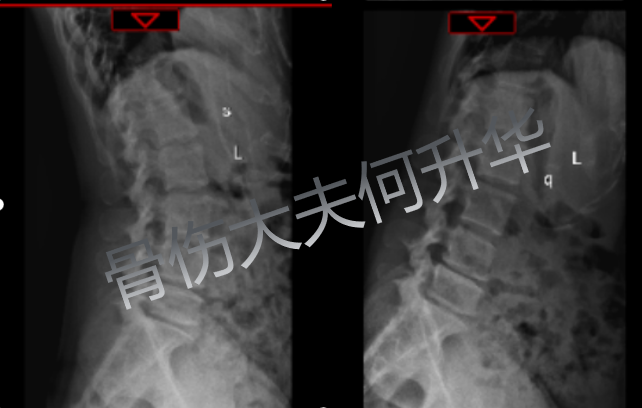

入院時(shí) X 線動(dòng)態(tài)體位提示

腰椎 4/5、腰椎 5/骶骨 1、椎間不穩(wěn)定